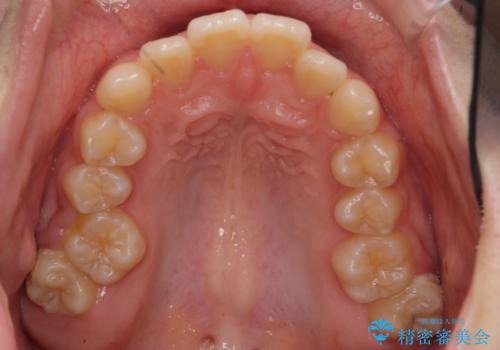

- 歯のがたつきを主訴に来院。

左右とも奥歯のがたつきがあり、左奥はすれ違っていました。

また、右奥は反対咬合になっていました。